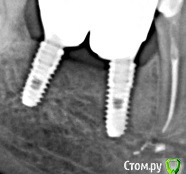

bullbull Опубликовано 27 августа, 2019 Поделиться Опубликовано 27 августа, 2019 2016 год 2019 Всё тот же осстем спустя 3 года. Может сделать времянки на полгода-год? Ссылка на комментарий

Nazim_NV86 Опубликовано 28 августа, 2019 Поделиться Опубликовано 28 августа, 2019 А для чего? Кость там, где ей и суждено быть. Вроде всё у вас неплохо там. Кортикалка сформирована. Ссылка на комментарий

Дмитрий М Опубликовано 29 августа, 2019 Поделиться Опубликовано 29 августа, 2019 2016.jpg2016 год 2019.jpg2019 Всё тот же осстем спустя 3 года. Может сделать времянки на полгода-год?кость уже не вернетсяпрофиль прорезывания Ссылка на комментарий